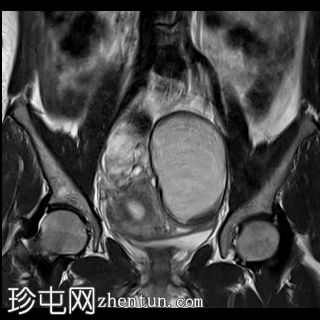

冠状位

T2快速加权像

左侧卵巢可见一巨大、无强化囊性病变。该病变壁薄,在T1加权像和T1脂肪抑制像上呈均匀高信号,在T2加权像上呈独特的阴影状,符合子宫内膜异位囊肿的特征。值得注意的是,该病变可见两个增强灶,但未见内部实性成分或对比增强。

此外,右侧卵巢内数个小的、无强化囊性病变表现出类似的信号特征,这也符合子宫内膜异位囊肿的特征。

双侧卵巢向内侧移位,形成“接吻卵巢征”。

子宫后壁子宫圆锥增厚,累及直肠前壁。

子宫、双侧卵巢和直肠因挛缩性粘连/纤维带而靠近,形成近期描述的深部盆腔子宫内膜异位症的“三叶草征”。

双侧卵巢出血性囊肿提示双侧子宫内膜异位囊肿,也称为巧克力囊肿。双侧卵巢位置接近,被称为“接吻卵巢”,这是由于粘连、子宫圆锥韧带和卵巢圆韧带增厚以及卵巢、直肠和子宫呈三叶草状排列所致,提示盆腔子宫内膜异位症。